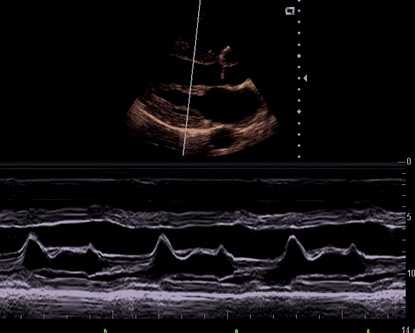

M型(Time-motion mode)

• 用于显示体内某一声束上各界面与探头的距离随时间变化的曲线。纵轴代表人体组织的深度,横轴代表这些不同深度的界面在某一段时间内的运动曲线。

• 主要应用在于心脏的检查,可将运动的心壁,血管壁或瓣膜的活动情况。

• 一般和B型同步显示。